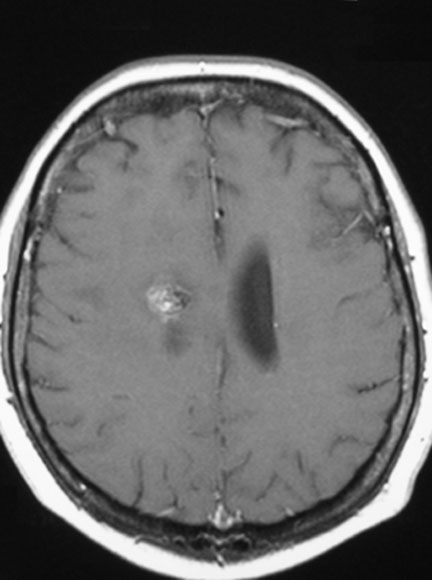

Metástasis Cerebral de cáncer de mama:

Paciente con tumor primario ( CA de mama ) controlado. Hace 1 año metástasis tratadas con radiocirugía en el extranjero. Viene con recurrencia con 2 metástasis. La paciente tiene trastorno del lenguaje (afasia) y parálisis del lado derecho del cuerpo (hemipléjia)

Resonancia magnética al momento de la intervención. Note el gran volumen tumoral y la compresión cerebral.